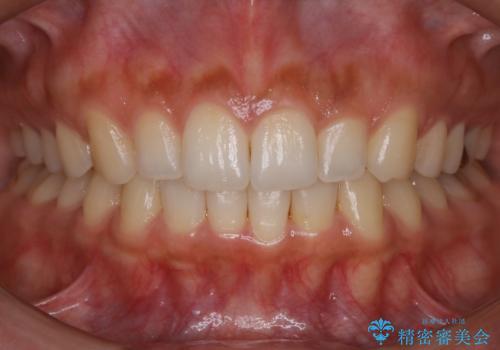

【非抜歯】前歯のガタつき マウスピースの部分矯正

- 上下の前歯の細かいガタつきの治療をご希望されて来院されました。

奥歯部分にはガタつきや噛み合わせの問題などがほとんど見られず、前歯のガタつきも軽度だったため、インビザライン ライト パッケージでの部分矯正を行うこととなりました。

今回のケースでは奥歯の噛み合わせに問題がほぼみられなかったため、前歯の位置のみに焦点を当て部分矯正を行いました。

適応されるケースが限られるものの、適応であった場合の治療期間は全体矯正と比べると格段に短くなり、費用も抑えられます。